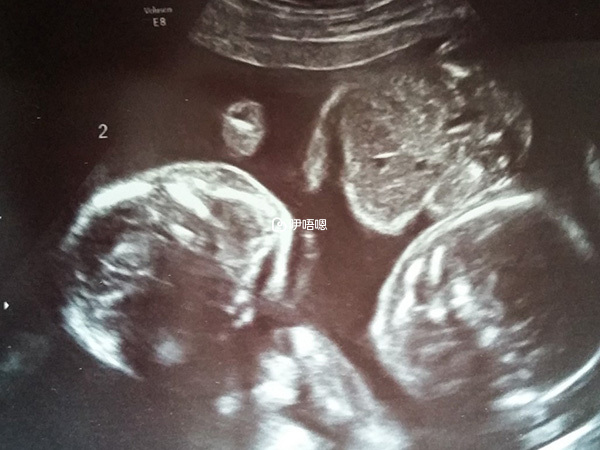

三天後去醫院量了血,第十三天HCG577,孕酮>40,我趕緊把好訊息告訴了傅醫生,他也好開心,並說我有可能是雙胎,因為HCG值很高。週一我做了第二次B超,得知是宮內雙活胎,跟我老公都樂了好幾天了!